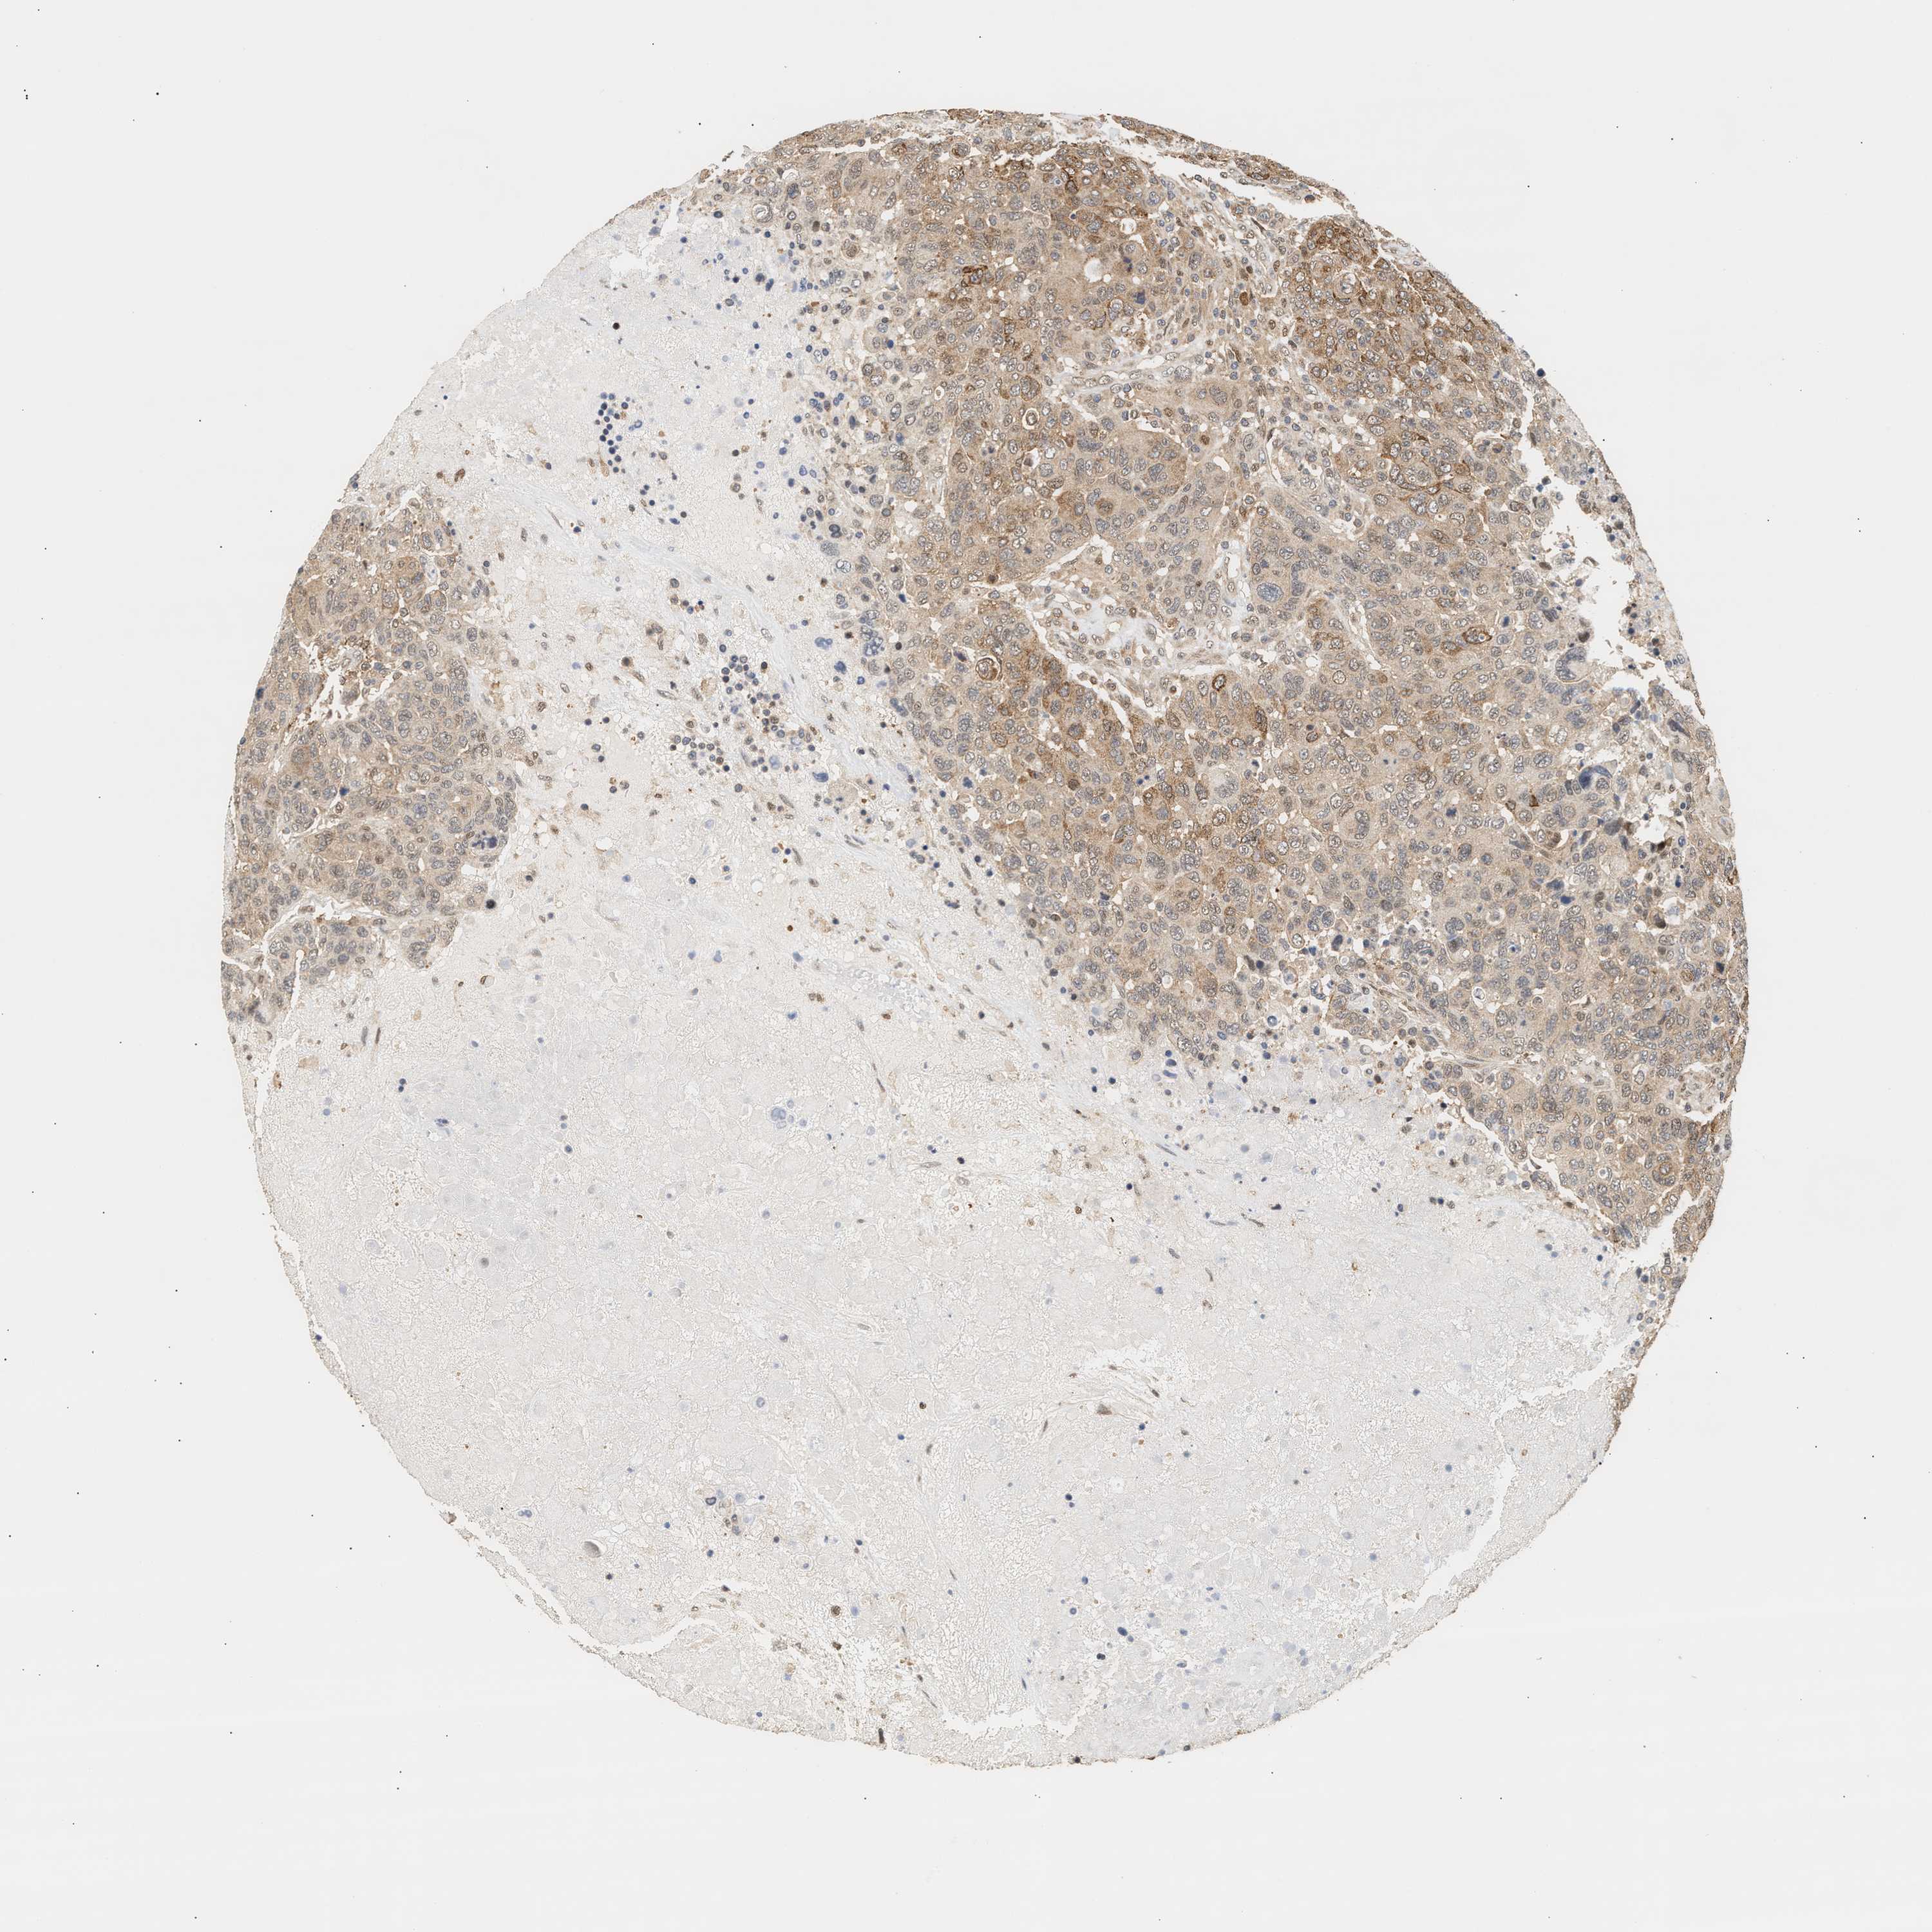

CANCER BREAST CANCER Show tissue menu

BRCA TCGA BRCA VALIDATION PROTEIN EXPRESSION

Breast cancer

Human cancer